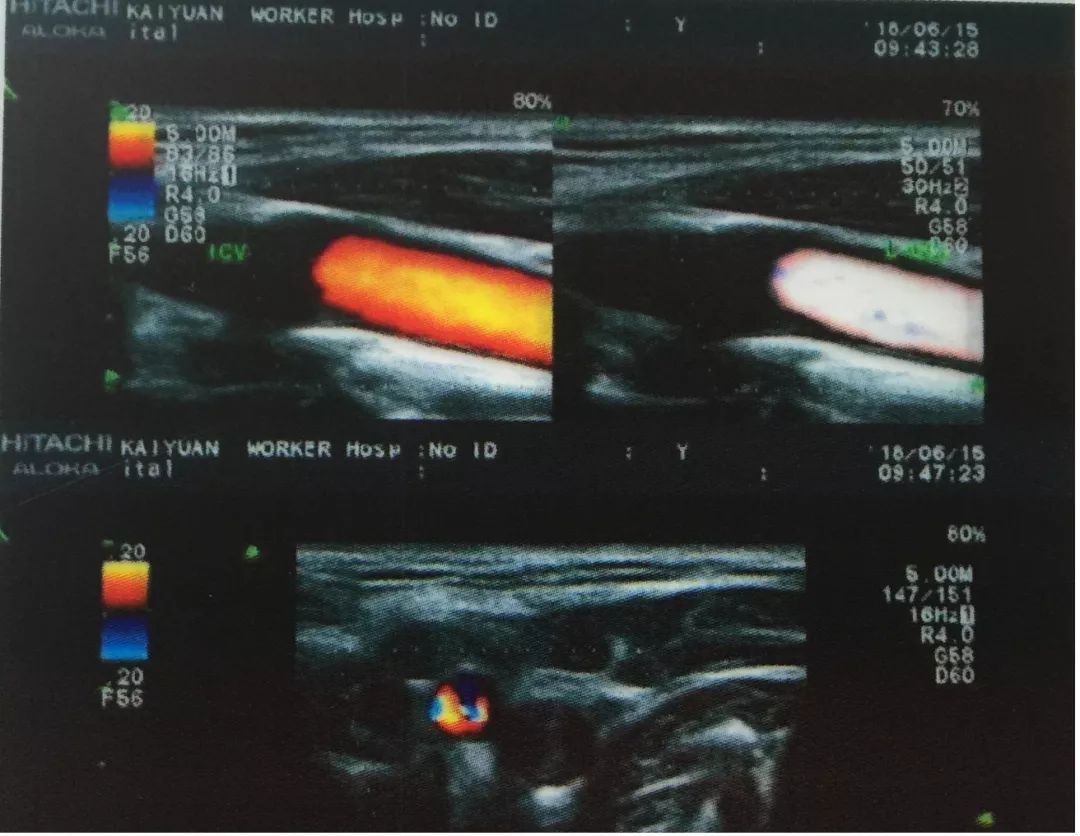

今年60岁的杨进聪,突然出现右侧肢体活动不灵,并伴有言语不清的症状。其从砚山县城迅速赶到开远工人医院就医,入院后,紫主任立即对他进行了颈部血管超声检查,发现其双侧颈总动脉粥样斑块形成(混合斑);右侧颈内动脉狭窄;左侧颈内动脉重度狭窄,甚至闭塞声像图;狭窄段收缩峰值明显增高,远端血流频谱呈“小慢波”。

图为左侧颈内动脉闭塞超声图谱,图片由功能科提供